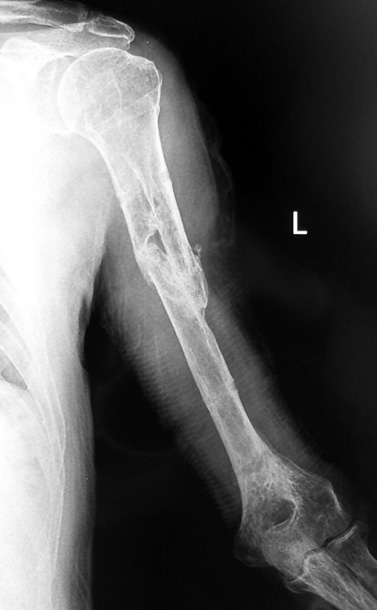

Humerus Psödartroz

Pseudarthrosis

Pseudarthrosis of fracture and pseudarthrosis treatment is currently important problem for orthopedic surgery. Various treatment modalities have been described for pseudarthrosis treatment. All of the treatment methods include high complication rates and additional problems. Leg-length discrepancy, deformity and soft-tissue loss and chronic infection can concomitance with pseudarthrosis. Many internal or external fixation techniques have been described for pseudarthrosis. Debridement and resection of bone fragment from the pseudarhtosis area vascularized or nonvascularized fibula graft, vascularized muscle flaps, bone grafting followed internal fixation techniques make a option for treatment of pseudarthrosis treatment. But these treatment modalities may not correct deformity and leg-length discrepancy. Recently, ilizarov techniques which is basis depend on distraction osteogenesis , bone segment transport or acute shortening after the resection at the site of pseudarthrosis combined with lengthening at another level of bone have been used. These treatment techniques may include some advantage for problems of infection, leg-length discrepancy, soft-tissue loss, and joint contracture.